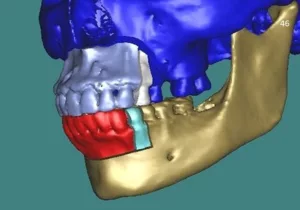

La Chirurgie assistée par ordinateur, guides et plaques sur mesure

On l’appelle plus communément « chirurgie guidée »

La chirurgie guidée consiste à simuler le geste opératoire au moyen de logiciels spécialisés puis à assurer le contrôle de l’exécution chirurgicale au bloc opératoire à l’aide de guides de découpe osseuse et de forage.

Des miniplaques en titane sur mesure spécifiques de l’anatomie propre à chaque patient et spécifiques des mouvements envisagés par le chirurgien permettent de stabiliser toutes les pièces anatomiques libérées par les manœuvres d’ostéotomie conformément à la simulation : plateau maxillaire, arc denté mandibulaire, branches montantes et condyles, menton .

Ostéotomie de Lefort I en 1, 2 ou 3 fragments, ostéotomie sagittale des branches montantes, génioplasties, ostéotomies segmentaires maxillaires et mandibulaires, postérieures ou antérieures, plus rarement ostéotomies de Lefort II ou Lefort III, tous les types d’ostéotomies peuvent être réalisés en chirurgie guidée.